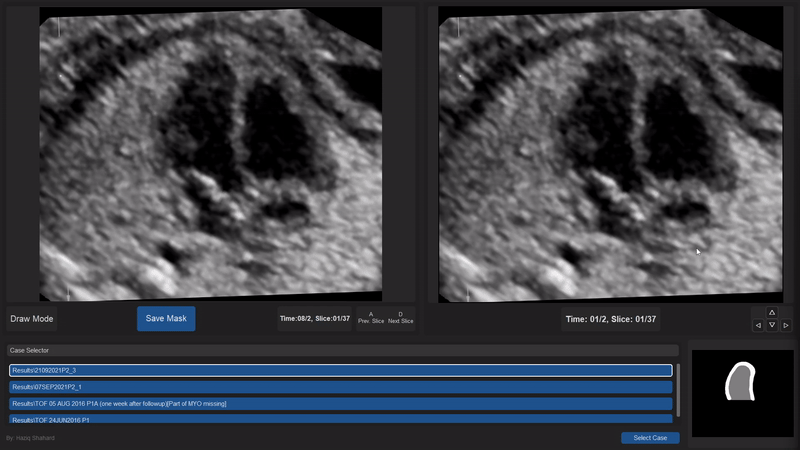

Manual Delineation Step

Using a custom-built annotation tool (details in our SegmentationApp), experts manually delineated the left ventricular myocardium and cavity by marking points along their boundaries (see video below). The tool supports 3D volume loading, interactive contour drawing, and real-time quality control through mask overlay. It also provides temporal navigation to capture cardiac motion, particularly valuable in cases affected by acoustic dropout, and annotation toggling for iterative refinement. To ensure accuracy and consistency, all annotations underwent multiple rounds of expert review followed by cardiologist validation.

Figure: Manual delineation of myocardium at ED and ES by SegmentationApp.